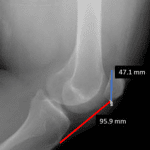

- No acute fracture

- Patella alta with extensive infrapatellar soft tissue swelling

- Moderate joint effusion

- Patellar tendon rupture

No acute fracture.

Patella alta with extensive infrapatellar soft tissue swelling. Findings raise concern for patellar tendon rupture. Recommend correlation with physical exam and consideration of MRI for further assessment.

Moderate joint effusion.

Joint spaces are maintained.